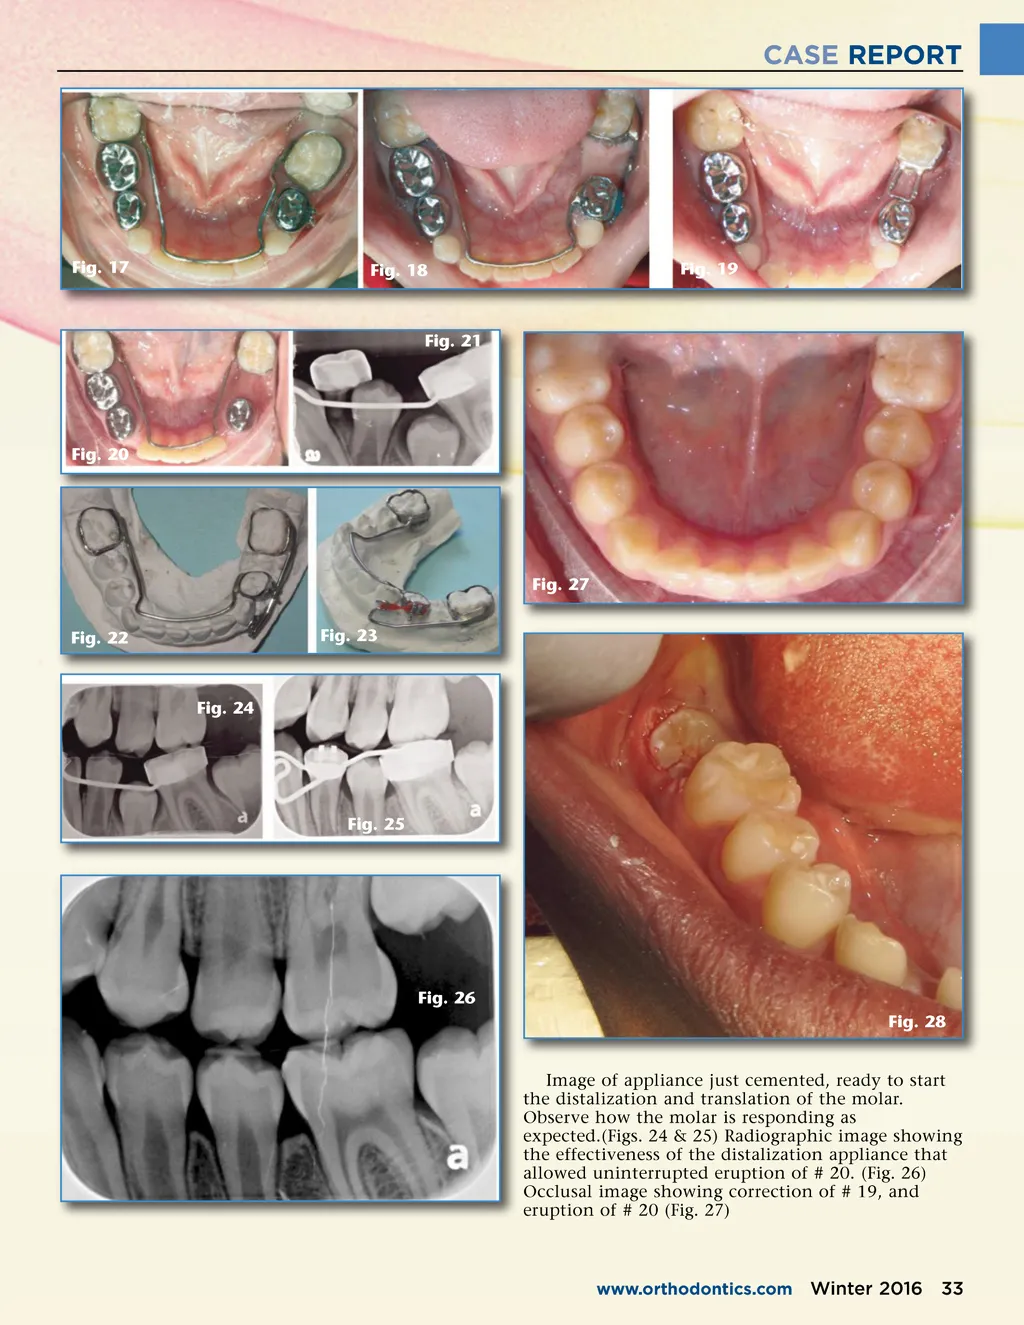

CASE REPORT Fig. 14 Fig. 11 Fig. 15 Fig. 12 Fig. 16 Fig. 13 and loop to allow for better plaque control by the patient and immediate stabilization of the space. Another acceptable option for a space retainer could have been a lower lingual arch.(Fig. 16) Images showing start end-point of correction and replacement with a band and loop. (Figs. 17, 18, & 19) The authors want to show a second case to demon-strate the flexibility of this design. In the following situation, the patient was at the end of the mixed dentition stage, and the second bicuspid was starting to be impacted preventing its eruption path. The etiology of this case was ectopic position and eruption of bicus-pids #20, 21. Second patient in late mixed dentition, ectopic erup-tion of bicuspids blocked out tooth # 20, and created the situation to be corrected. Radiograph shows ectopic eruption of the bicuspids. (Figs. 20 & 21) Two views of distalization appliance on model ready for placement on patient. At time of cementation the distal portion of the appliance should be cemented first. The lower lingual arch is cemented last.(Figs. 22 & 23) Case 2 32 Winter 2016 JAOS